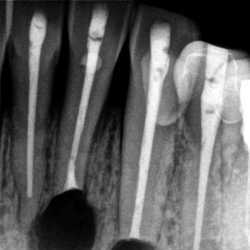

Inicio Especialidades Endodontia